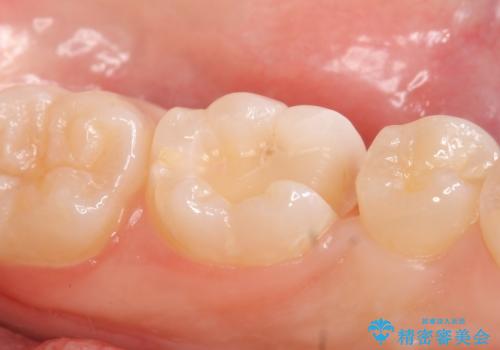

- 左下奥歯がしみるので診て欲しいといらっしゃった方の症例です。

古い樹脂と虫歯を除去後、セラミックインレーによる修復を行いました。